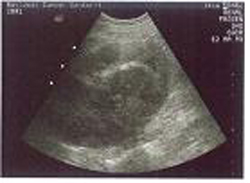

복부초음파검사

2009.08.20